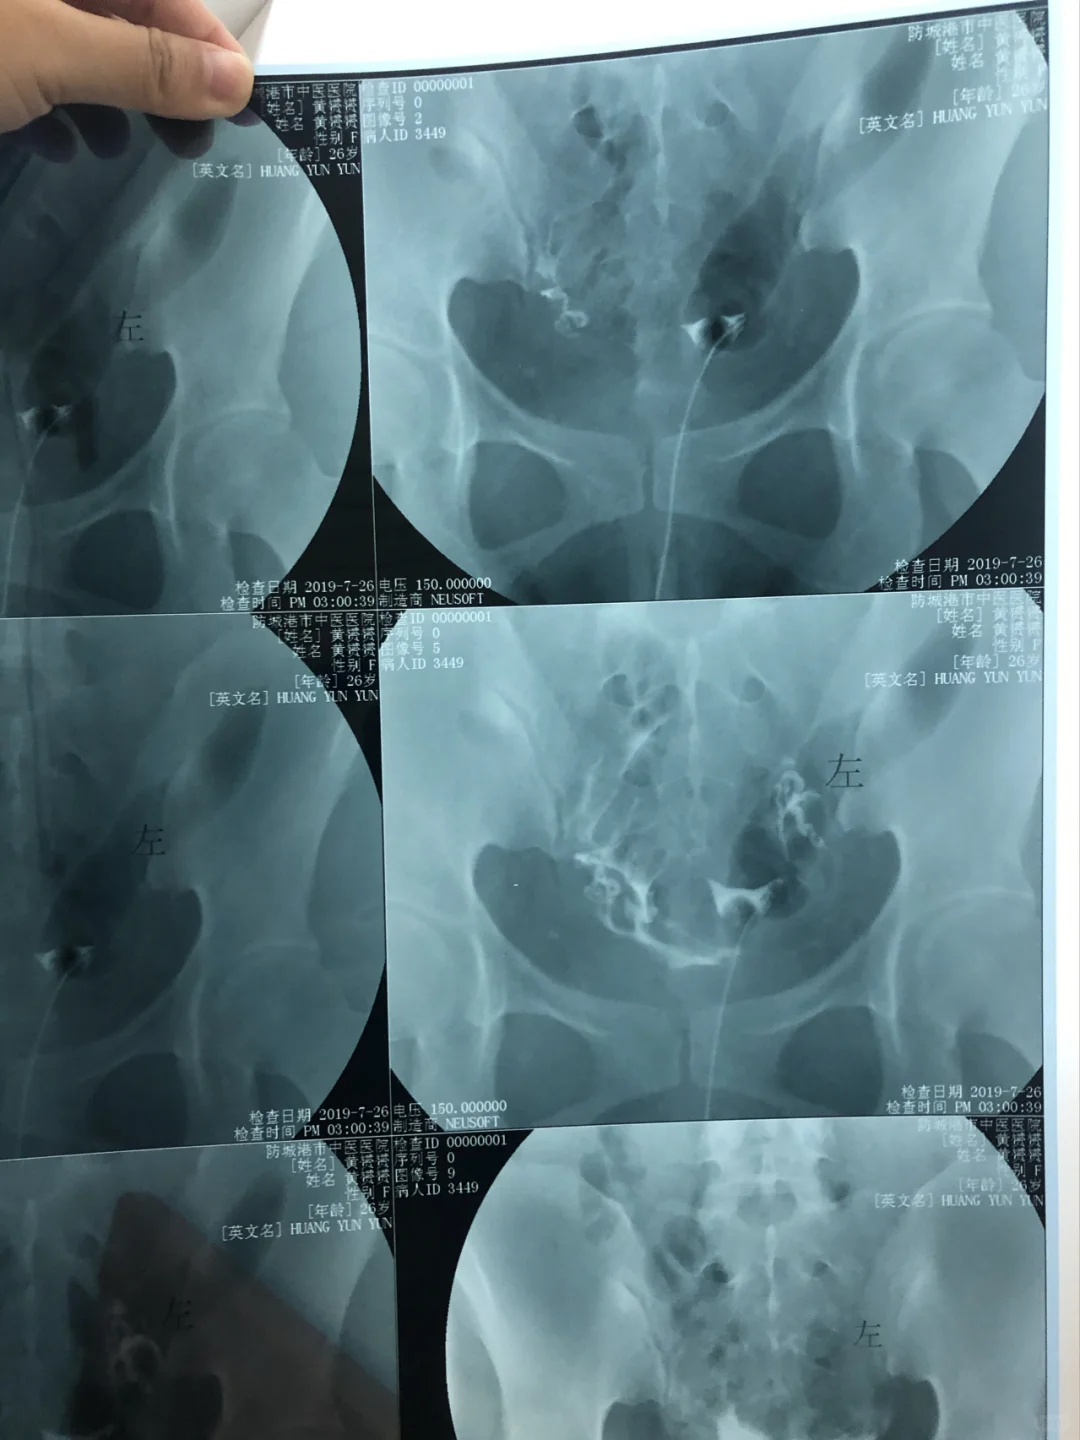

多囊卵巢综合症,男女双方检查所有没问题,促排三次不中,不知道怎么办,无意间问了抖音医生!结果给她看了输卵管片子后,居然说我迂曲上举!更慌了!马上去问了周围的医生,以及自己的主治医生!都说没有问题!在群里问小姐妹,姐妹马上说她也问过!也说输卵管有问题!结果没几天小姐妹都已经怀孕了,7月份都生了!举报了...